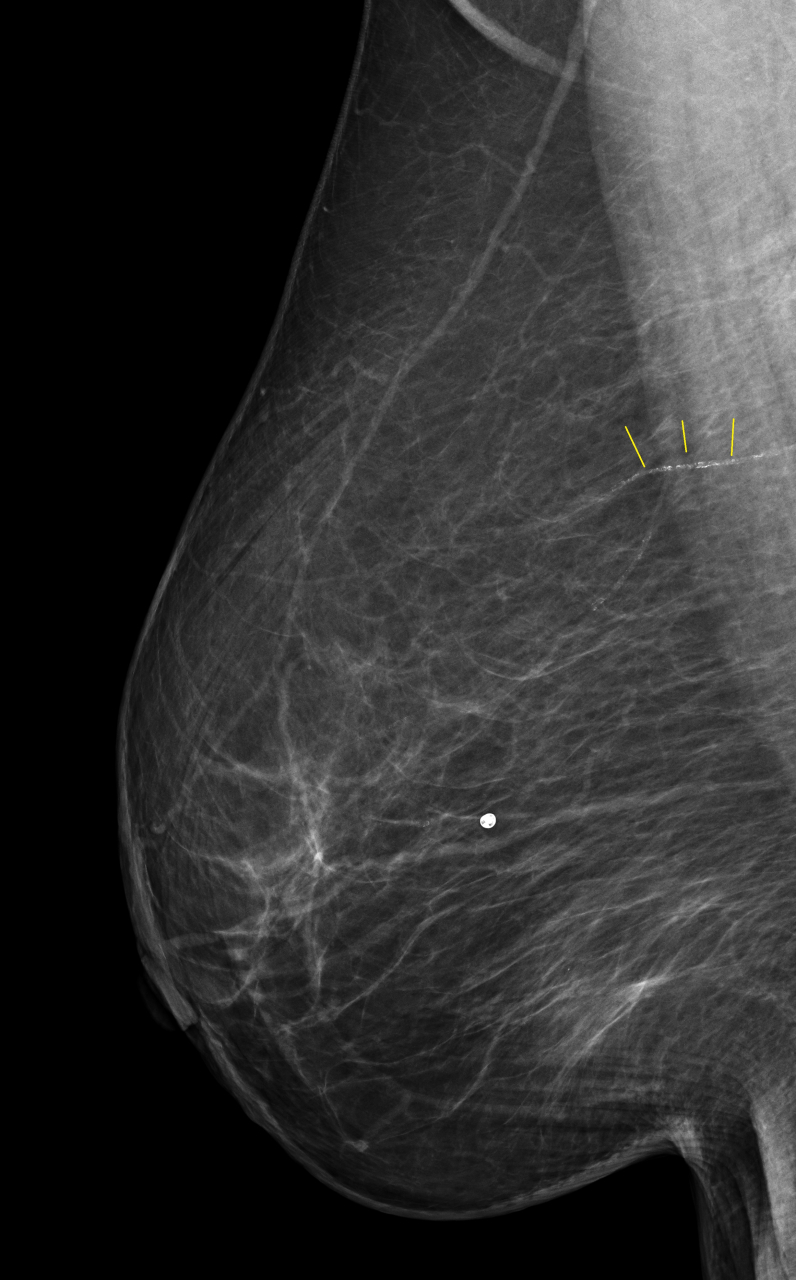

上記のMMGにおいて 黄色い線で示しているところは乳腺の動脈です。そこに沿って白い小さな点がびっしりと認められます。この動脈に”動脈硬化”が発生し、そこに石灰(カルシウム)が沈着することで描出されるようになったものです。